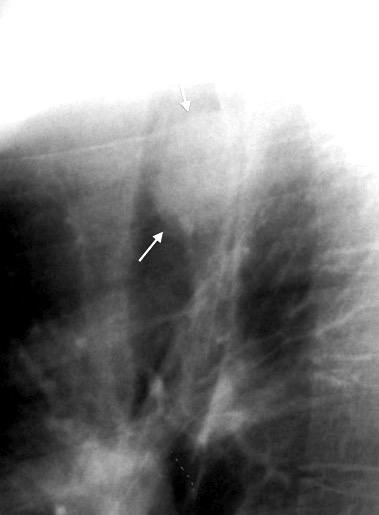

30 años

Borramiento de la banda PARA-aórtica por AdenoCa. de LII, no visible en 2005

Colapso de LII. TC: secreciones bronquiales.

Endoscopia tapón mucopurulento extraído

Borramiento parcial por Ca. epidermoide.